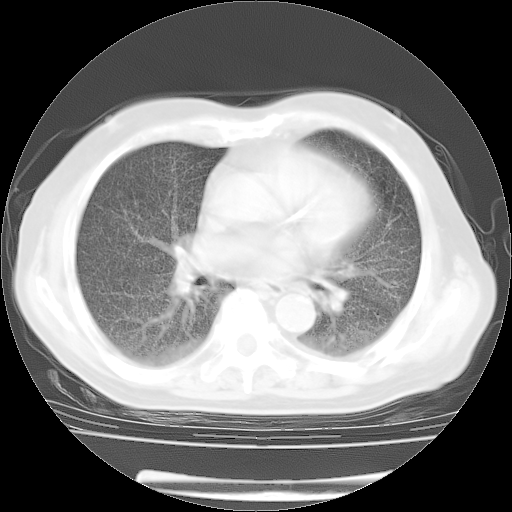

4月14日肺部CT